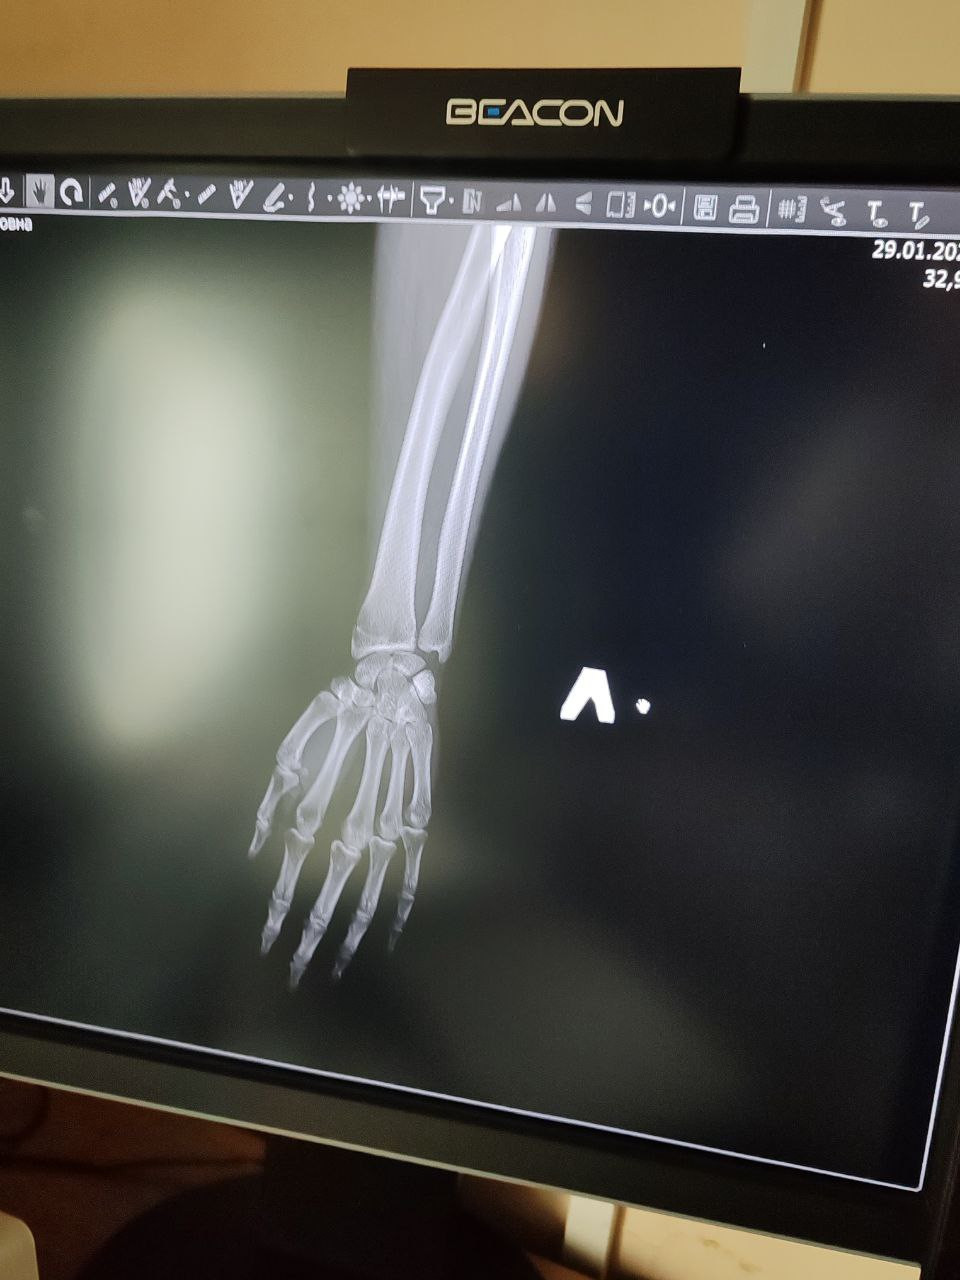

Здравствуйте, 28.01 ударила руку сначала рука не сильно болела, а теперь с каждым днём всё хуже, 29.01 сделали снимки врачи в травмпункте утверждают что просто ушиб , ранее 2 года назад мне ставили дисторсию лучезапястного сустава и я ходила в гипсе , сейчас же при очень сильных болях рекомендаций никаких нету , рука опухшая, больно шевелить , прикреплю снимки рентгена, надеюсь на вашу помощь , скажите пожалуйста что нужно делать (меня смущает на снимке расстояние между косточками) так же часто немеют пальцы и ощущается пульс в руке

Здравствуйте. По снимкам явного перелома не видно, но описанные боли, отёк, онемение и «расстояние между косточками» могут указывать на повреждение связок лучезапястного сустава. Для уменьшения боли сейчас нужна фиксация кисти ортезом или бинтом, покой, холод 2-3 раза в день и НПВС по возрасту. Обязательно повторный осмотр травматолога, при необходимости МРТ т.к связочные травмы на рентгене часто не видны. Можно УЗИ  оно позволяет оценить связки, сухожилия и наличие отёка. Но при сохраняющейся сильной боли и онемении МРТ информативнее.